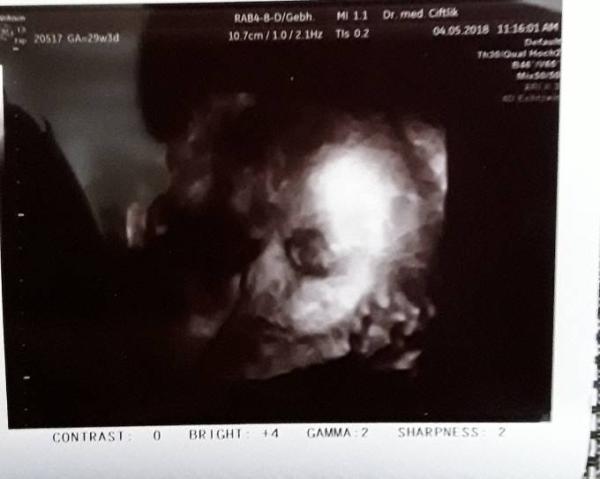

Hallo ihr Lieben, ich bin derzeit nur noch sporadisch hier aktiv, wollte euch aber auch meinen 3. Großen US nicht vorenthalten. Leider mussten die Fotos diesesmal ausgedruckt werden, da das Gerät noch defekt ist. Deshalb erkennt man nicht viel. Also sie liegt ganz brav in SL, juhu. sie ist ca 38,5cm groß und wiegt 1200g. Alles ist super Zeitgemäß Entwickelt und liegt im normalen Bereich. Die Ärztin sagt es ist definitiv kein dickes Kind und ich hoffe das bleibt so.

Auf dem Foto hat sie den rechten Arm unter der Wange, das ergibt diese knuffigen pausbacken, ich bin so verliebt in sie

. Die Augen sind zum Teil offen und wenn man ganz genau hinschaut, erkennt man eine pupille!